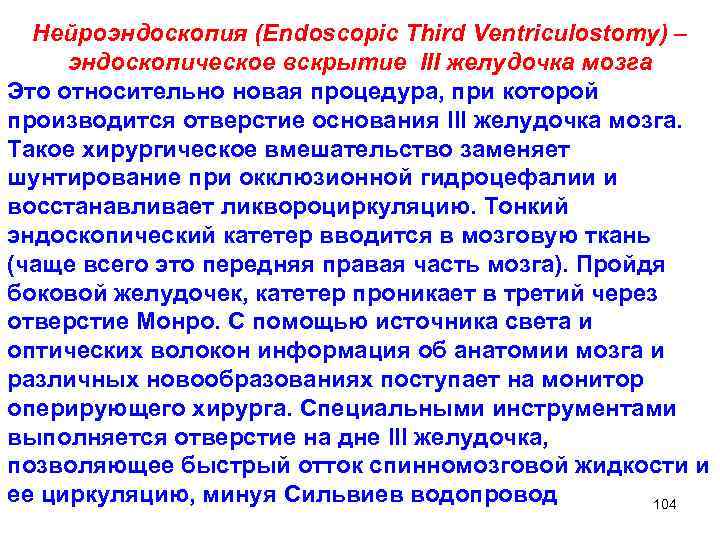

Нейроэндоскопия (Endoscopic Third Ventriculostomy) – эндоскопическое вскрытие III желудочка мозга Это относительно новая процедура, при которой производится отверстие основания III желудочка мозга. Такое хирургическое вмешательство заменяет шунтирование при окклюзионной гидроцефалии и восстанавливает ликвороциркуляцию. Тонкий эндоскопический катетер вводится в мозговую ткань (чаще всего это передняя правая часть мозга). Пройдя боковой желудочек, катетер проникает в третий через отверстие Монро. С помощью источника света и оптических волокон информация об анатомии мозга и различных новообразованиях поступает на монитор оперирующего хирурга. Специальными инструментами выполняется отверстие на дне III желудочка, позволяющее быстрый отток спинномозговой жидкости и ее циркуляцию, минуя Сильвиев водопровод 104

Условия и показания для Endoscopic Third Ventriculostomy: - пациент старше двух лет с суженным Сильвиевым каналом; - цисты или опухоли, закрывающие или сужающие проход Сильвиев водопровод; различные патологии, нарушающие нормальный отток спинномозговой жидкости из IV желудочка (Арнольд Киари или Дэнди Уокер) 105